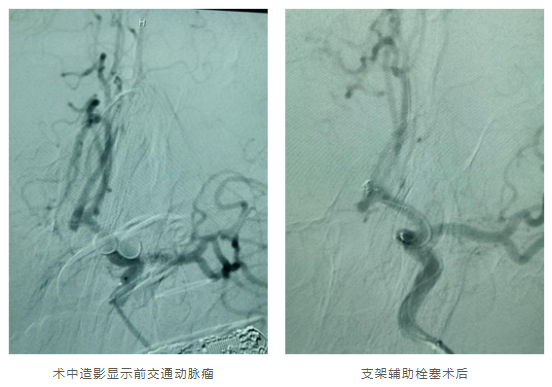

这台手术后叶明教授并未休息,而是连续又做了1台大脑中动脉瘤双微导管栓塞术和2台前交通动脉瘤支架辅助栓塞术。

第4台手术的患者是1名57岁男性,患者在3年前行CTA提示前交通动脉瘤,当时动脉瘤的直径是2.1mm,定期复查检查CTA未见明显变化,20天前复查CTA发现动脉瘤较前增大,为进一步诊治要求入神经外科进一步治疗。经过近2个小时的努力,手术顺利结束。

from clipboard